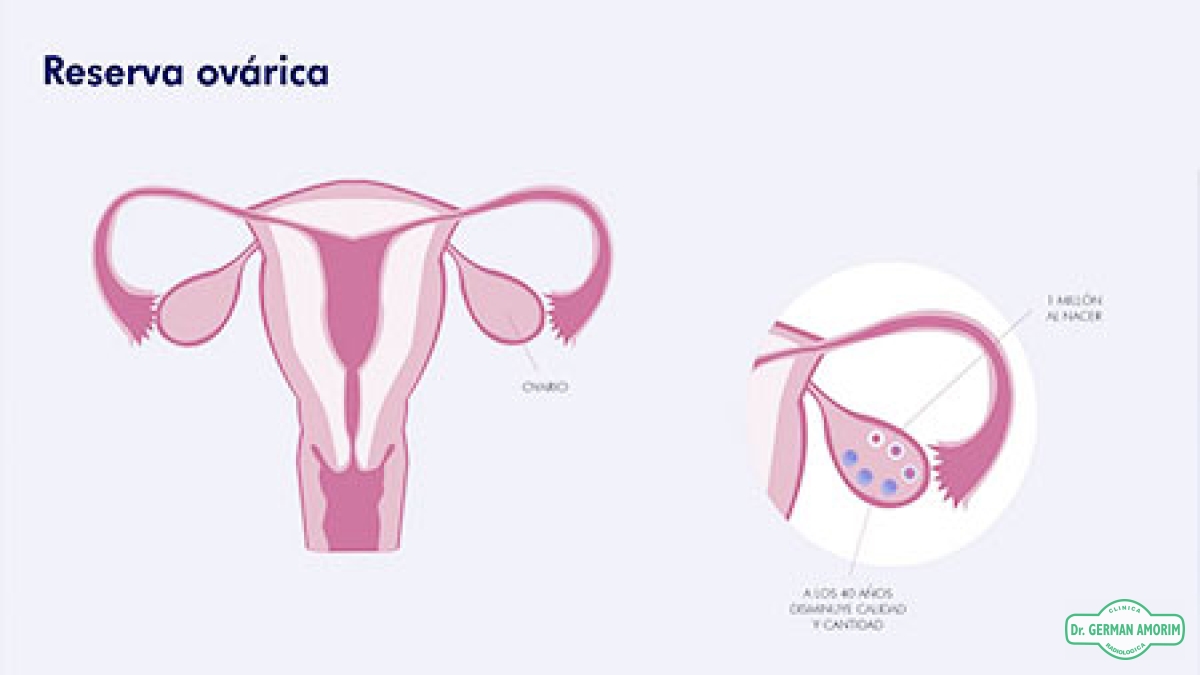

La reserva ovárica refleja el potencial fértil de la mujer.

A diferencia de los hombres, que producen espermatozoides a lo largo de toda la vida, las mujeres nacen con un número determinado de óvulos. Al llegar a la pubertad, la mujer comienza a ovular todos los meses; en el momento de la menopausia, la reserva de óvulos ha quedado agotada y consecuentemente la mujer pierde la fertilidad.